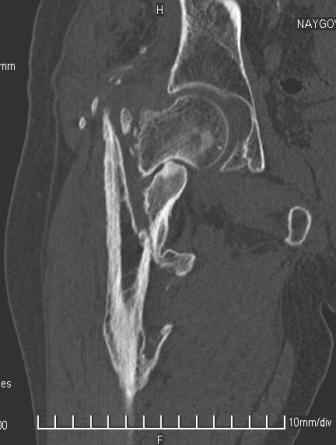

Больной Н. 44 года травма 1,5 года назад июнь 2008 года чрез-под вертельный перелом правого бедра. Во время лечения у больного развился алк. делирий, проводилось консервативное лечение перелома.

Беспокоят боли, укорочение конечности.Укорочение 3 см. Ногу поднимает, сгибание ограничено, ротационные движения в полном объеме.На КТ перелом сросся за счет костной мозоли.Что делать?

Протез? Если «да» Можно ли обойтись стандартной ножкой Corail?

Или межвертельная остеотомия?